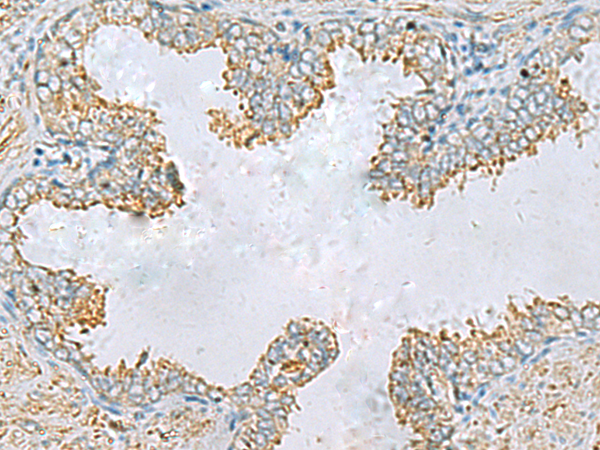

分类: 科研抗体货号: P10359别名: GODZ; DHHC3; DHHC-3; ZNF373应用: IHC反应种属: Human, Mouse

分类: 科研抗体货号: P10357别名: GNT-IV; GNT-IVB应用: IHC反应种属: Human, Mouse

分类: 科研抗体货号: P10356别名: SAMP32应用: IHC反应种属: Human

分类: 科研抗体货号: P10363别名: CT46.2应用: IHC反应种属: Human

分类: 科研抗体货号: P10355别名: ACS; LLPL; LPLA2; LYPLA3; GXVPLA2应用: IHC反应种属: Human, Mouse, Rat